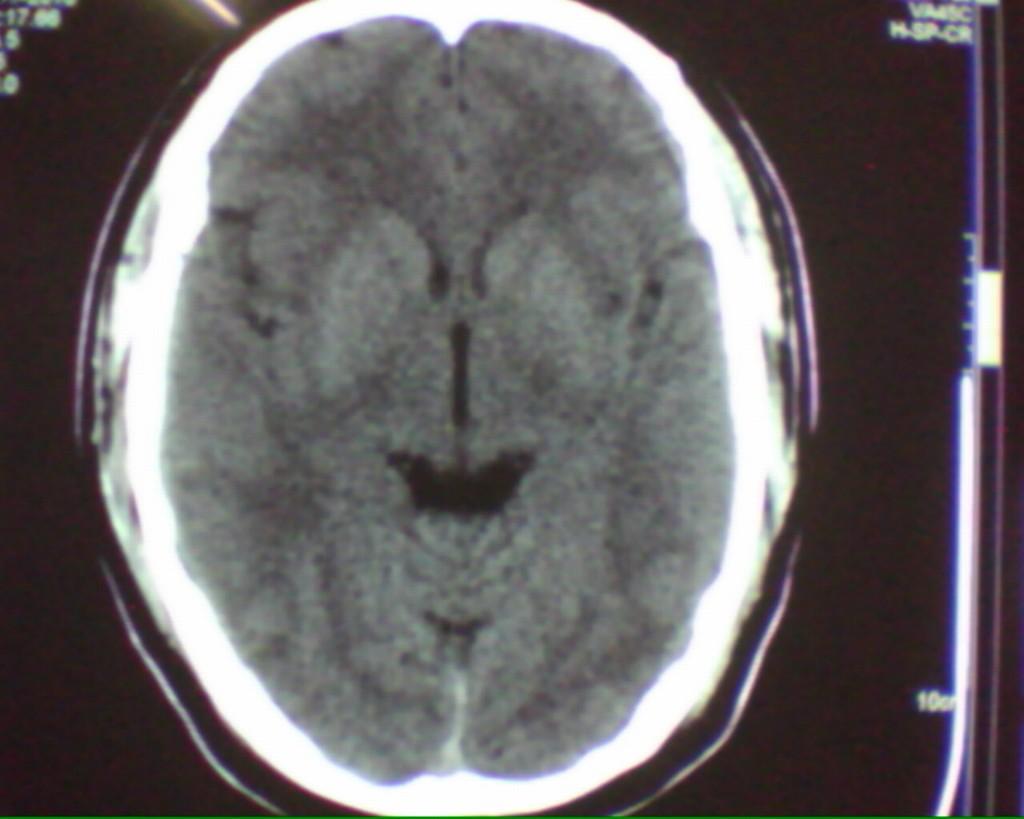

男性52岁,头部外伤,左侧眼睑及颧骨部软组织肿胀,ct发现左侧额部颅骨同板下有条状高密度影,我仔细看了一下,还是考虑伪影,主要原因是 该条状高密度影与颅骨内板有低密度影相隔,如是硬膜下或硬膜外出血,不可能出现该低密度间隔,请大家把这个病例讨论一下,谢谢。

应该是伪影,颅骨是圆形弧状的,层面较厚是常出现此种伪影的,薄层扫描就不会出现此种伪影

结合自己平时遇到的病例考虑了一下,觉得还是考虑硬膜外小血肿更合适一些:首先此病人头白的位置较对称,对侧没有发现,其次受伤的部位正是此处,再次所谓的间隙如果血肿较小恐怕未必。前不久本人就遇到类似的情况,经薄层重建及随访证实确是血肿,所以建议楼主还是薄层或随访复查为上策。

伪影,常见。为弧顶部分容积效应,虽然跟小血肿似乎难鉴别,但是小血肿那么大边界没有那么清楚,